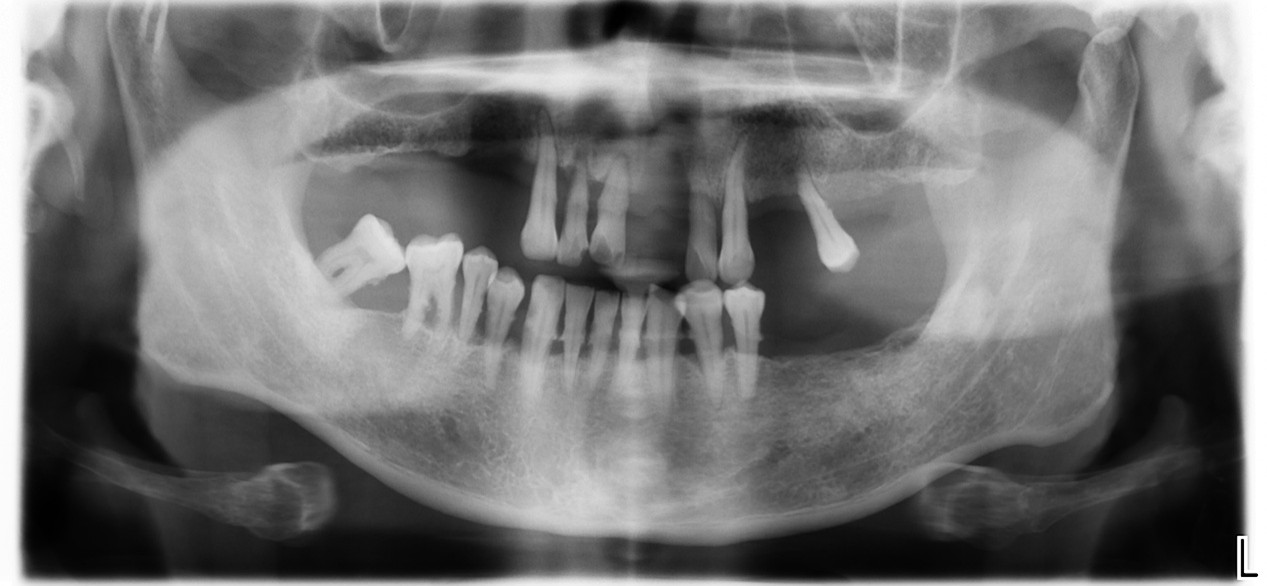

不需要進行補骨手術

ALL on 4 & 6只有挑有骨頭條件好的地方植牙,沒有骨頭的地方(上下顎後牙區)刻意將植牙避開沒有骨頭區域,因此不需要補骨。